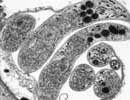

Cryptosporidium_hominis_37999 Courtesy of Saul Tzipori, Tufts

Comment:Cryptosporidium hominis is the dominant species which infects humans. Although generally self-limiting, this disease can cause fatalities in children and immunocompromised adults. The genome sequence of Cryptosporidium hominis shows features consistent with its life cycle as an obligate parasite. This organism lacks the genes necessary for the production of a number of biochemical building block such as nucleotides and amino acids. To compensate for this lack, the genome contains a large number of transporter or transporter-like genes.